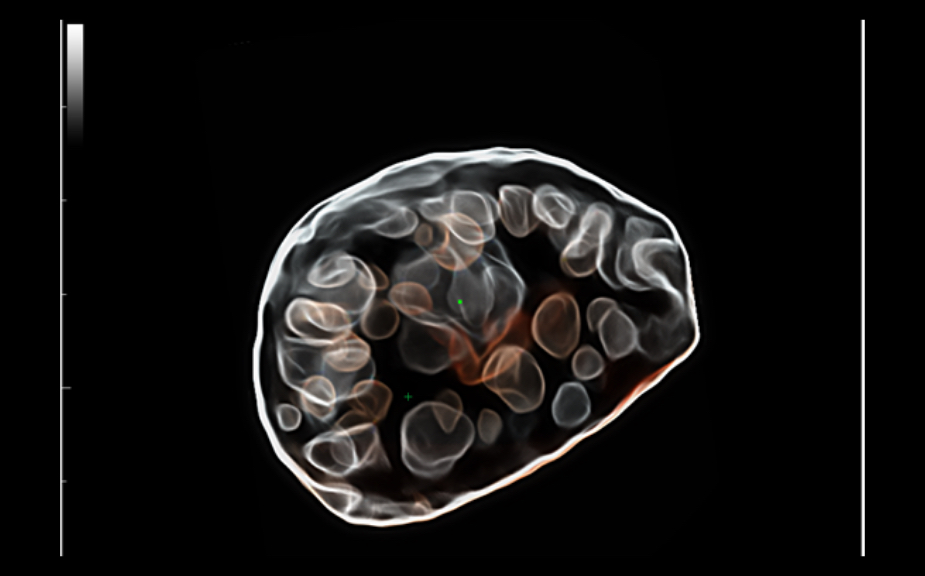

ImĂĄgenes clĂnicas